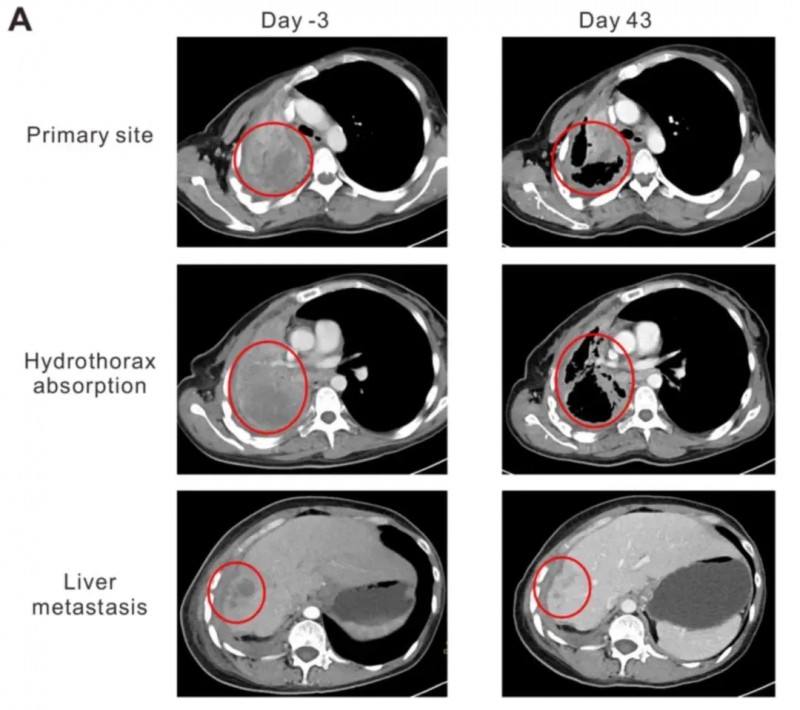

尤为值得关注的是患者2的治疗历程:该患者为44岁HLA-A2阳性、携带EGFR突变的NY-ESO-1阳性晚期肺腺癌(LADC)女性,此前经六个周期多西他赛+卡铂联合化疗,以及吉非替尼、厄洛替尼治疗均效果不佳,疾病持续进展。2015年9月随访CT显示,其右肺门、纵隔、右胸膜、右肝叶及肝包膜均出现转移进展(PD),临床已无更合适治疗方案。幸运的是,右肺肿瘤支气管镜活检显示免疫组化染色呈强NY-ESO-1阳性,使其成功入组TCR-T治疗。

结果显示:首次TCR-T细胞输注后第43天(2016年1月)的CT扫描显示,患者肺原发灶及肝转移灶开始消退,胸水吸收、肺复张:肺原发灶从95×86×54mm缩小至64×44×54mm,肝转移灶由19.8×19.6×20mm缩小至10×10×10mm,依据RECIST1.1标准评价达到部分缓解(PR)。同时,患者卡氏功能状态评分(KPS)从输注前的50分提升至90分,咯血、胸痛症状明显缓解,临床症状得到显著改善。

▲图源“Oncology Letters”,版权归原作者所有,如无意中侵犯了知识产权,请联系我们删除